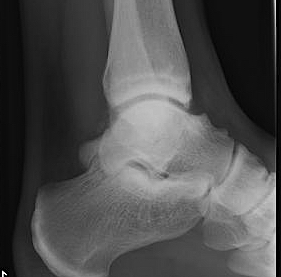

Xray

Anterior tibial and talus spurs with normal joint space